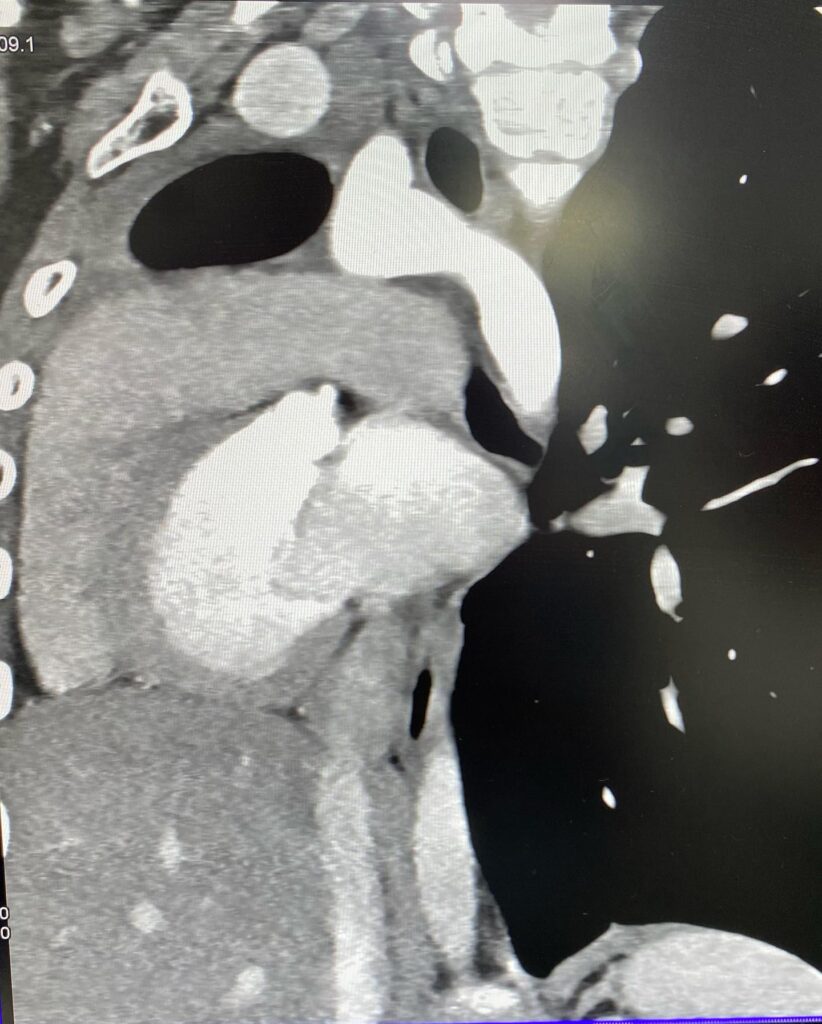

««Նորք-Մարաշ» բժշկական կենտրոն դիմելիս 14–ամյա տղայի գանգատը եղել է աջ կողմից սրտխփոցի զգացումը (մայրիկի խոսքերով՝ երեխան դա նկատել է դեռ 1 տարի առաջ ֆուտբոլ խաղալիս)։ Էխոսրտագրության ժամանակ երեխայի սիրտը աջից էր, սակայն դա սովորական դեկստրակարդիա չէր, ինչը բժշկի մոտ կասկած առաջացրեց, որի կապակցությամբ կատարվեց կրծքավանդակի կոնտրաստ համակարգչային տոմոգրաֆիա։

Արդյունքը տպավորիչ էր։ Երեխայի մոտ առկա էր աջ թոքի ագենեզիա (թոքը չի զարգացել, համապատասխանաբար բացակայում էին նաև աջ գլխավոր բրոնխը, աջ թոքային զարկերակը և աջ թոքային երակները), ինչի հետևանքով միջնորմը (այդ թվում սիրտը) տեղակայված է կրծքավանդակի աջ կեսում։ Սրտի նման տեղակայումը հեմոդինամիկ շեղումներ չի առաջացրել. երեխան ունի կառուցվածքային առողջ սիրտ։ Երեխան ուղեգրվել է թոքաբանի և օրթոպեդի խորհրդատվության, իսկ «Նորք-Մարաշ» ԲԿ-ում կլինի դինամիկ հսկողության տակ»,- հայտնում են «Նորք-Մարաշ» ԲԿ-ից։